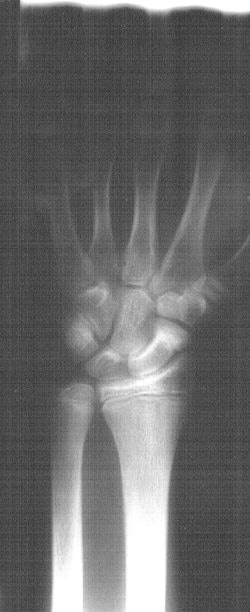

![]() |

| Sixteen weeks post-injury and eight weeks post-application of Exogen device, there is evidence of healing. |